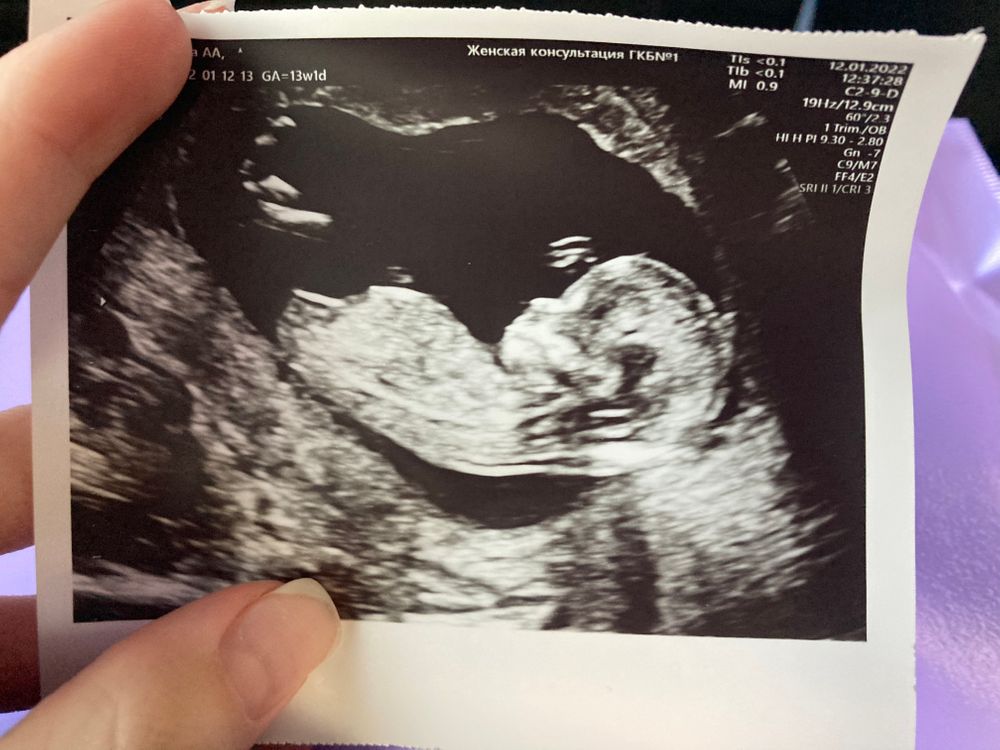

Мне на первом скрининге в 13 недель не сказали, узистка сказала что на втором скрине узнаю🥴🤦‍♀️ я купила фотку, по ней я думаю девочка будет. А вообще, пойду в 15 недель (через недельку), там уже должно быть видно точно. Изображение